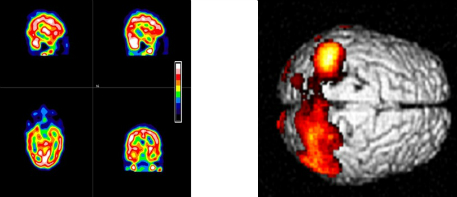

Quantitative analysis of radionuclide imaging of the brain

The group has an established record of designing, validating and implementing a range of quantitative methods of analysing DaTSCAN datasets. With their high binding affinity for pre-synaptic dopamine transporters (DAT), these scans are able to diagnose Parkinson’s disease and offer a differential diagnosis over other neurological disorders with a similar clinical presentation. The group has experience of using regional uptake, shape and pattern recognition to aid the diagnosis.

Cerebral perfusion imaging is currently attracting renewed interest, as a result of the possibility of drug treatment of Alzheimer’s disease. Imaging provides a valuable method of objectively assessing the response to treatment and also the possibility of aiding and confirming diagnosis. We have pioneered the routine clinical use of statistical parametric mapping (SPM) and other quantitative and highly-sensitive approaches to image analysis of these scans, enabling response and diagnosis to be called with greater confidence.

On the left are typical three dimensional gamma camera images of cerebral perfusion displayed in pseudo colour. On the right is an example of the output from SPM analysis, showing areas with significantly reduced perfusion indicative of disease.